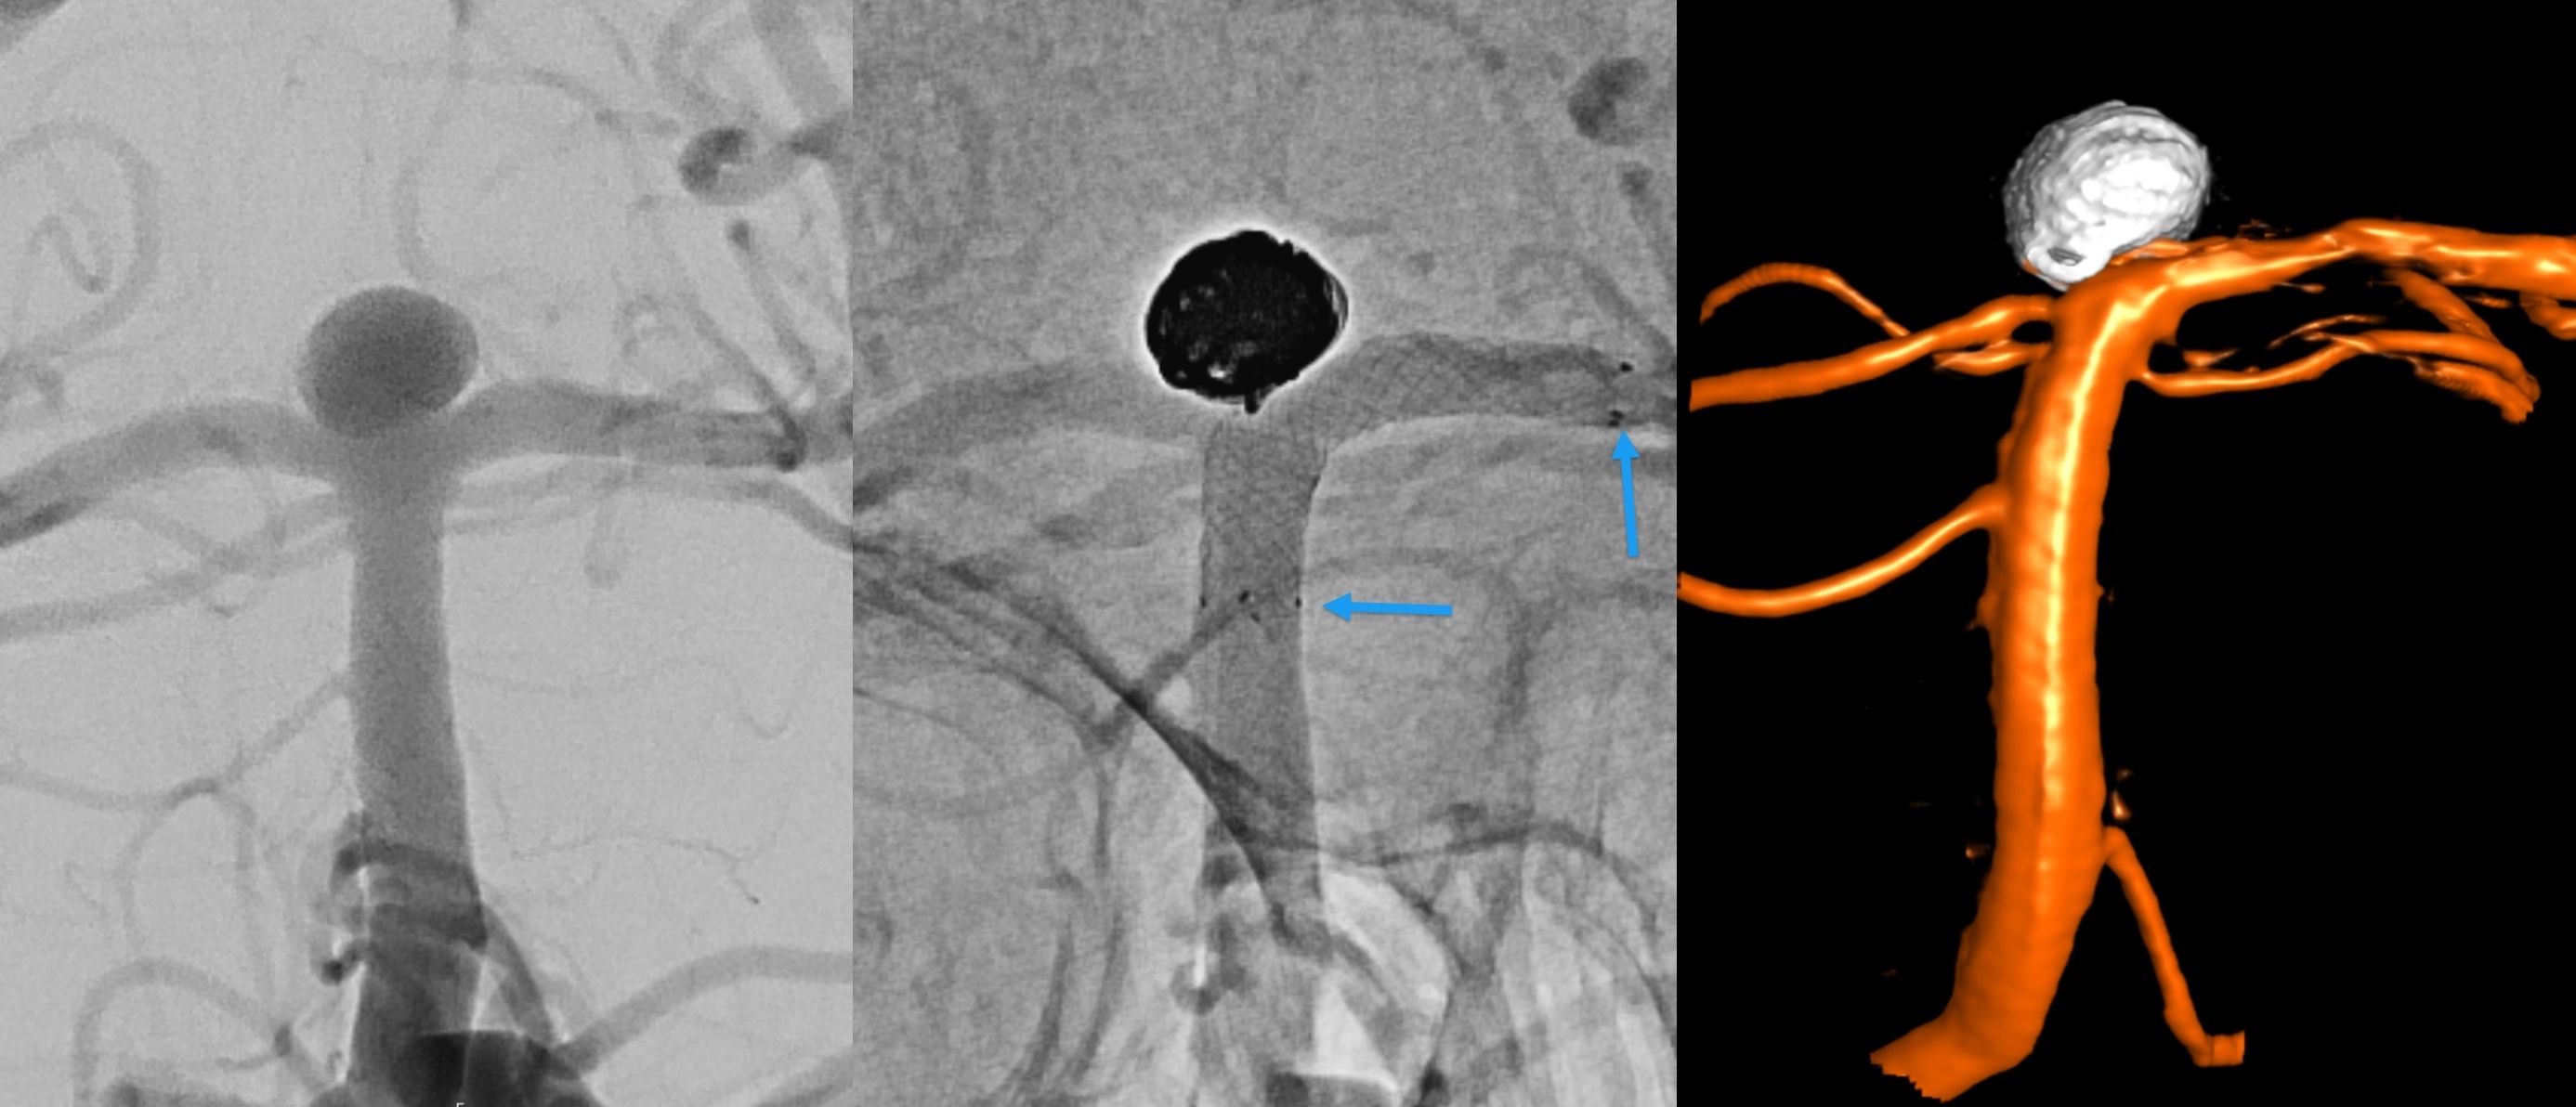

Ein wichtiger Meilenstein in der Neuro-Intervention war die Einführung der sogenannten ablösbaren Platinspiralen ("Coils") Anfang der 1990er Jahre. Diese Innovation ermöglichte erstmals den minimal-invasiven Verschluss von intrakraniellen Aneurysmen (krankhafte Gefässerweiterungen im Gehirn). Damit veränderte sich die Behandlung von Blutungen im Gehirn (hämorrhagische Pathologien) grundlegend. Die Technik entwickelt sich kontinuierlich weiter: Moderne Werkzeuge wie Remodelling-Ballons, Stents und Flow-Diverter ermöglichen heute die effektive Versorgung selbst komplexester Aneurysmen.